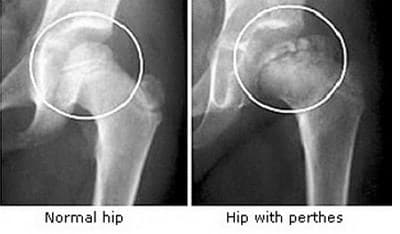

Perthes Disease